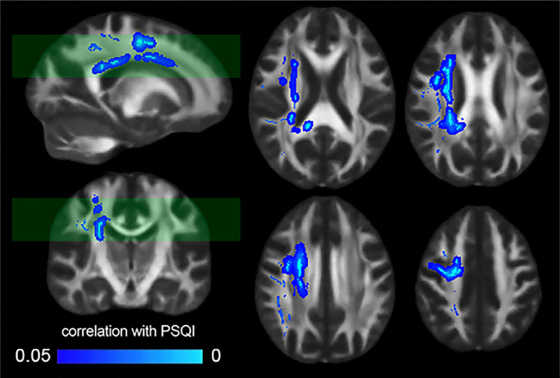

今回の研究では人の脳の画像データと動物実験を組み合わせて、睡眠不足と「白質」という髄鞘が多い領域の関係が分析されました。まず185人分の脳MRIデータでは、睡眠の質を自己申告で評価する指標「Pittsburgh Sleep Quality Index(PSQI)」のスコアが悪いほど、白質の指標が低い傾向が広い範囲で見られたとのこと。